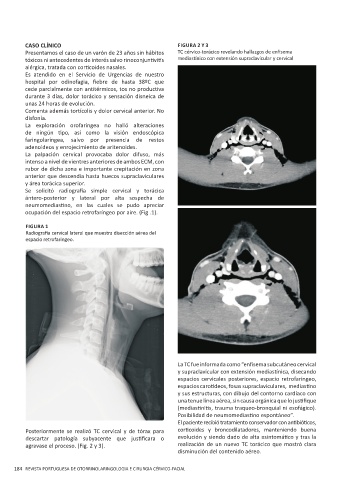

CASO CLÍNICO FIGURA 2 Y 3

Presentamos el caso de un varón de 23 años sin hábitos TC cérvico-torácico revelando hallazgos de enfisema

tóxicos ni antecedentes de interés salvo rinoconjuntivitis mediastínico con extensión supraclavicular y cervical

La TC fue informada como “enfisema subcutáneo cervical

y supraclavicular con extensión mediastínica, disecando

espacios cervicales posteriores, espacio retrofaríngeo,

espacios carotídeos, fosas supraclaviculares, mediastino

y sus estructuras, con dibujo del contorno cardíaco con

una tenue línea aérea, sin causa orgánica que lo justifique

(mediastinitis, trauma traqueo-bronquial ni esofágico).

Posibilidad de neumomediastino espontáneo”.

Posteriormente se realizó TC cervical y de tórax para corticoides y broncodilatadores, manteniendo buena

descartar patología subyacente que justificara o evolución y siendo dado de alta asintomático y tras la

agravase el proceso. (Fig. 2 y 3). realización de un nuevo TC torácico que mostró clara